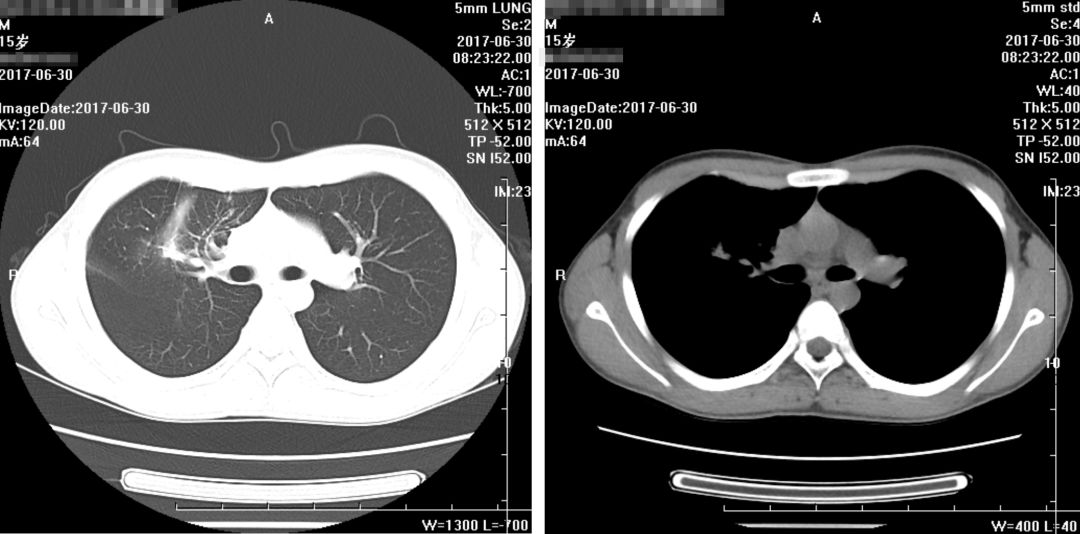

出院前一天,患者CT片结果如下:(2017年6月30日):

出院之后,家属不放心,又在门诊陆续复查了几次,且看患者恢复情况: